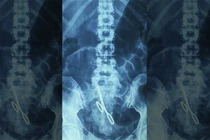

Bệnh nhân nữ giấu tên 44 tuổi này được xác định là trải qua một ca phẫu thuật nhỏ tại bệnh viện tư nhân San Camilo ở Madrid. Sau đó 2 ngày, bệnh nhân đến bệnh viện tái khám, các bác sĩ phát hiện hình ảnh chiếc kéo trong bụng bệnh nhân, thông qua ảnh chụp X-ray.

Ảnh chụp chiếc kéo bị bỏ quên bên trong bụng bệnh nhân.